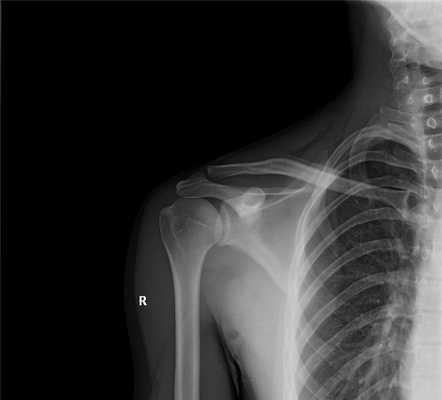

Рентген в двух проекциях (прямой и осевой) довольно чётко может показать отклонение текущего состояния плечевого сустава от нормы. На снимках можно увидеть, насколько смещена головка плечевой кости, каково направление её смещения, а также наличие переломов костей (если они есть). С помощью рентгена можно определить тип вывиха и предположить развитие возможных осложнений. Не допускается вправлять вывих без предварительного проведения рентгена.

Снимки показывают двухмерное изображение исследуемой области. На рентгенограммах хорошо видны структуры сустава, часть плечевой кости, пояс верхней конечности, состоящий из лопатки и ключицы.

При изучении результатов рентгена плеча врач может выявить признаки таких заболеваний:

- травмы костно-хрящевых структур - внутрисуставные переломы плеча, переломы ключицы и лопатки, переломы хирургической шейки плечевой кости;

- вывихи и подвывихи плечевого сустава;